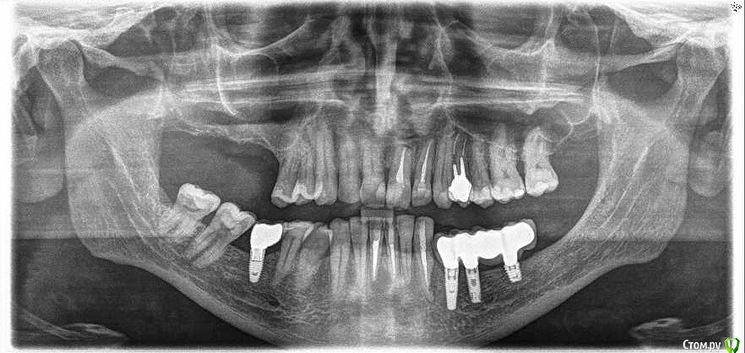

Jurai Опубликовано 25 декабря, 2016 Поделиться Опубликовано 25 декабря, 2016 *Предупреждение: фото на "мыльницу", не все этапы удались, но я работаю над этим) Вот пациент. Приятнейший, во всех отношениях, с негативным отношениям к мостовидным конструкциям. Полтора года лечил 41з по поводу периодонтита: толку не вышло. Удалил у широко известного многим стоматологам, особенно выпускам последних годов, доктора с ученой степенью. После удаления 4 месяца, по КТ область вполне достойно выглядит. Вот с чем пришел, обычное дело, все прилично: Раскрываю, а там между тонкими кортикалками мягко и упруго - резидуальная, фото нет. Открываю сильнее чем обычно, с расстройства не особо удачно. Кюретаж : Вид после, ушла вестибулярная кортикальная вместе с кистой: Сверлим 2,0, позиционердля рентген-контроля Имплантат ADIN UNP2,75Х11,5мм Ауто, джейсон коллагенфлис (что было под рукой) Швы. Контроль, перещелкивать не стали. В общем, понравился имплантат, для себя пометку кюретажить тщательнее, не надеяться, что организм все переварит. 1 9 Ссылка на комментарий

Jurai Опубликовано 26 декабря, 2016 Автор Поделиться Опубликовано 26 декабря, 2016 Как вообще впечатления от Адина?Я скажу откровенно - двойственные впечатления. Да, непафосно, да, просто, да, бывают резорбции по шейке. Но за три года, что я с ними работаю, в минусе два, ставлю почти исключительно Swell. Один вывернулся при вот такой картине Второй убрала при такой, трепаном еле выпилила, полчаса возиласьЕдинственное, я их ставлю только там, где можно хоть саморез по гипсокартону ввернуть и он интегрируется, то бишь, в идеальные условия. Ссылка на комментарий

Jurai Опубликовано 15 марта, 2024 Автор Поделиться Опубликовано 15 марта, 2024 Рекол! 7 лет в нагрузке. Нужно уточнить, что у пациента кошмарный прикус, 3 класс. 10 1 2 Ссылка на комментарий